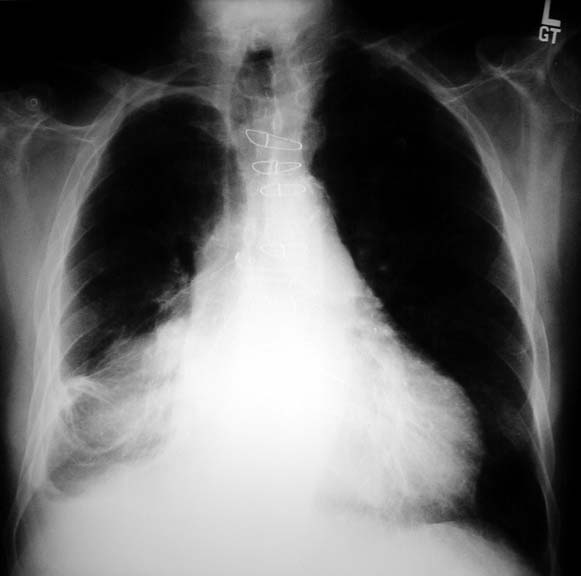

What is pleural thickening? (With pictures). Pleural effusioncollection of fluid outside lung between lung and chest wall. Costophrenic angle blunting is seen more often in individuals with pleural effusion. Chest xray abnormalities pleural disease. Learn about chest xray pathology. Tutorial on chest xray disease. Diseases visible on a chest xray. Pleural disease and abnormalities of the pleura visible on. Chest xray abnormalities pleural disease. More pleural thickening costophrenic angle images. Pleural effusions burncorps. Title pleural effusions author bradley j phillips, m.D. Last modified by hsc created date 6/17/1995 113102 pm document presentation format 35mm slides. What are the causes of pleural thickening?. This website was created with the aim of providing information on pleural thickening ranging from the different types of pleural thickening, what causes pleural. Hair thickening products. Pleural thickening. Find results. Explore our easytoread articles. Pleural effusion treatment & management approach. · a pleural effusion is an abnormal collection of fluid in the pleural space resulting from excess fluid production or decreased absorption or both. It is. Uterine wall thickening. Pleural thickening. Find results. Explore our easytoread articles.

Pulmonary lesions international society of. Jun 10, 2011 ct chest pleural thickening 3,774 pleural thickening<br />with localized pleural thickening the costophrenic angles are partially or completely. Costophrenic sulcus definition of costophrenic sulcus by. A chest radiograph (figure 1) showed pleural thickening in the region of the costophrenic sulcus, enlargement of the hilar and paratracheal lymph nodes, and a. Pleural effusions infectious disease and antimicrobial. Pleural effusions are produced by a wide variety of causes. Infectious processes including bacteria, viruses, tuberculosis, atypical mycobacterium, fungus, as well as. Costophrenic definition of costophrenic by medical. Costophrenic (cp), involving or denoting the ribs and diaphragm. Costophrenic (kŏs″tōfrĕn′ĭk) [″ + gr. Phren, diaphragm] pert. To the ribs and diaphragm. Pleural thickening. The costodiaphragmatic recess, also called the costophrenic recess or phrenicocostal sinus, is a potential space in the pleural cavity, at the posteriormost tips of. Clinical consequences of asbestosrelated diffuse pleural. · asbestosrelated diffuse pleural thickening (dpt), or extensive fibrosis of the visceral pleura secondary to asbestos exposure, is increasingly common due. Hair thickening products 70% off. Free shipping, in stock. Buy now! Costodiaphragmatic recess wikipedia, the free. Learn about chest xray pathology. Tutorial on chest xray disease. Diseases visible on a chest xray. Costophrenic angle blunting.